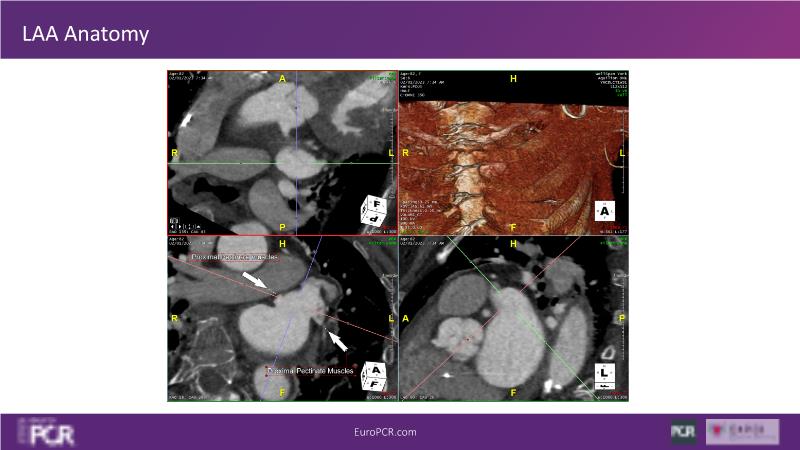

Explore this session to discover the latest innovations in interventional cardiology images, including the benefits of artificial intelligence and angio-CT in PCI/SHD procedures. Learn about Alphenix Evolve and the initial experiences with AI imaging in daily cathlab practice, alongside intraprocedural angio-CT guided LAAO, and engage in discussions on meaningful tools that can transform patient care.